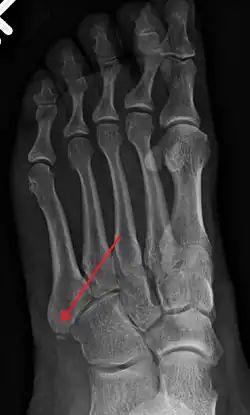

Fracture of the base of the 5th metatarsal

The metatarsal bones are often broken by association football (soccer) players. These and other recent cases have been attributed to the lightweight design of modern football boots, which provide less protection to the foot. In 2010 some football players began testing a new sock that incorporated a rubber silicone pad over the foot to provide protection to the top of the foot.[8] Stress fractures are thought to account for 16% of injuries related to sports participation, and the metatarsals are the bones most often involved. These fractures are sometimes called march fractures, based on their traditional association with military recruits after long marches. The second and third metatarsals are fixed while walking, thus these metatarsals are common sites of injury. The fifth metatarsal may be fractured if the foot is oversupinated during locomotion.[9]